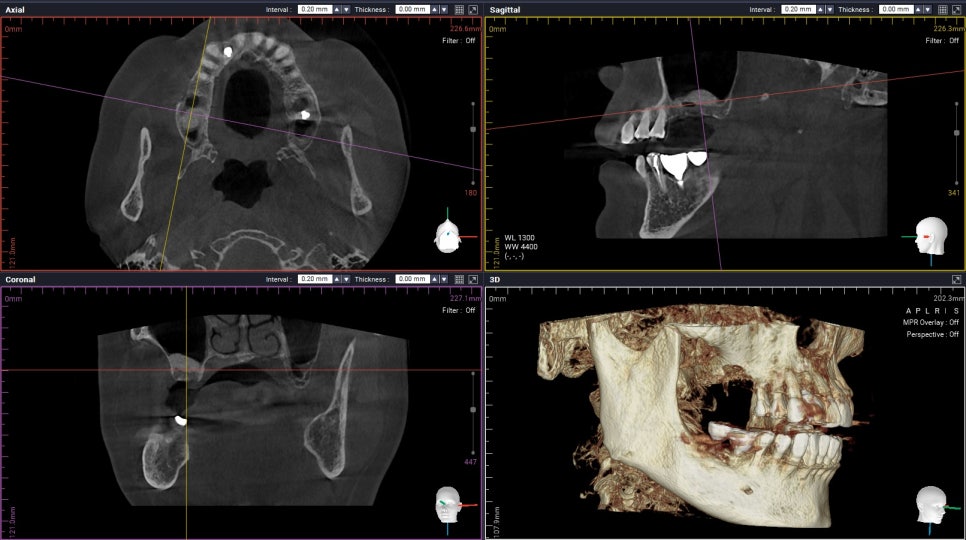

(세번째 케이스)

Periodontally involved teeth

Following implant placement with sinus graft

이 환자분의 경우

우측 위 어금니를 발치하고나서

충분히 기다린 후

수술을 진행 하셨는데요,

염증이 있던 치아 였기에

뼈이식을 충분히 하고

수술을 진행했습니다 :)

Confirmation with CBCT

간혹

상악동 거상을 하면

기간이 얼마나 걸리는지

문의주시는 분들이 계신데요,,,

사실 저희도

빨리 해드리면 좋지만 ㅠ.ㅠ

충분한 고정력을 얻고

성공적인 임플란트 수술을 위해

이처럼

뼈이식 양이 많은경우에는

약 5~6개월 정도 기다린 후

최종보철물이 올라가게 됩니다.